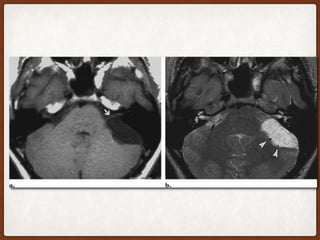

EPIDERMOID CYST • Alsoknown as primary cholesteatomas . • Their growth is due to accumulation of keratin and cholesterol produced by desquamation of the squamous epithelium lining the mass. • These slow-growing tumors encase and surround nerves and arteries rather than displacing them. • On CT, they appear hypo or almost isoattenuating to CSF . • Characteristic irregular lobulated margins . • No reaction of adjacent bone structures as opposed to arachnoid cysts.

• 10.

• At MRimaging, epidermoid cysts have slightly higher signal intensity than CSF on T1- and T2- weighted images, often with heterogeneous and marbled features . • FLAIR is more sensitive than conventional sequences in differentiation of epidermoid and arachnoid cysts because it suppresses the signal of CSF. • With this sequence, epidermoid cysts have high signal intensity, whereas the signal of arachnoid cysts is suppressed. • DWI can also be used to differentiate from arachnoid cyst. • Epidermoids show diffusion restriction .

• 13.